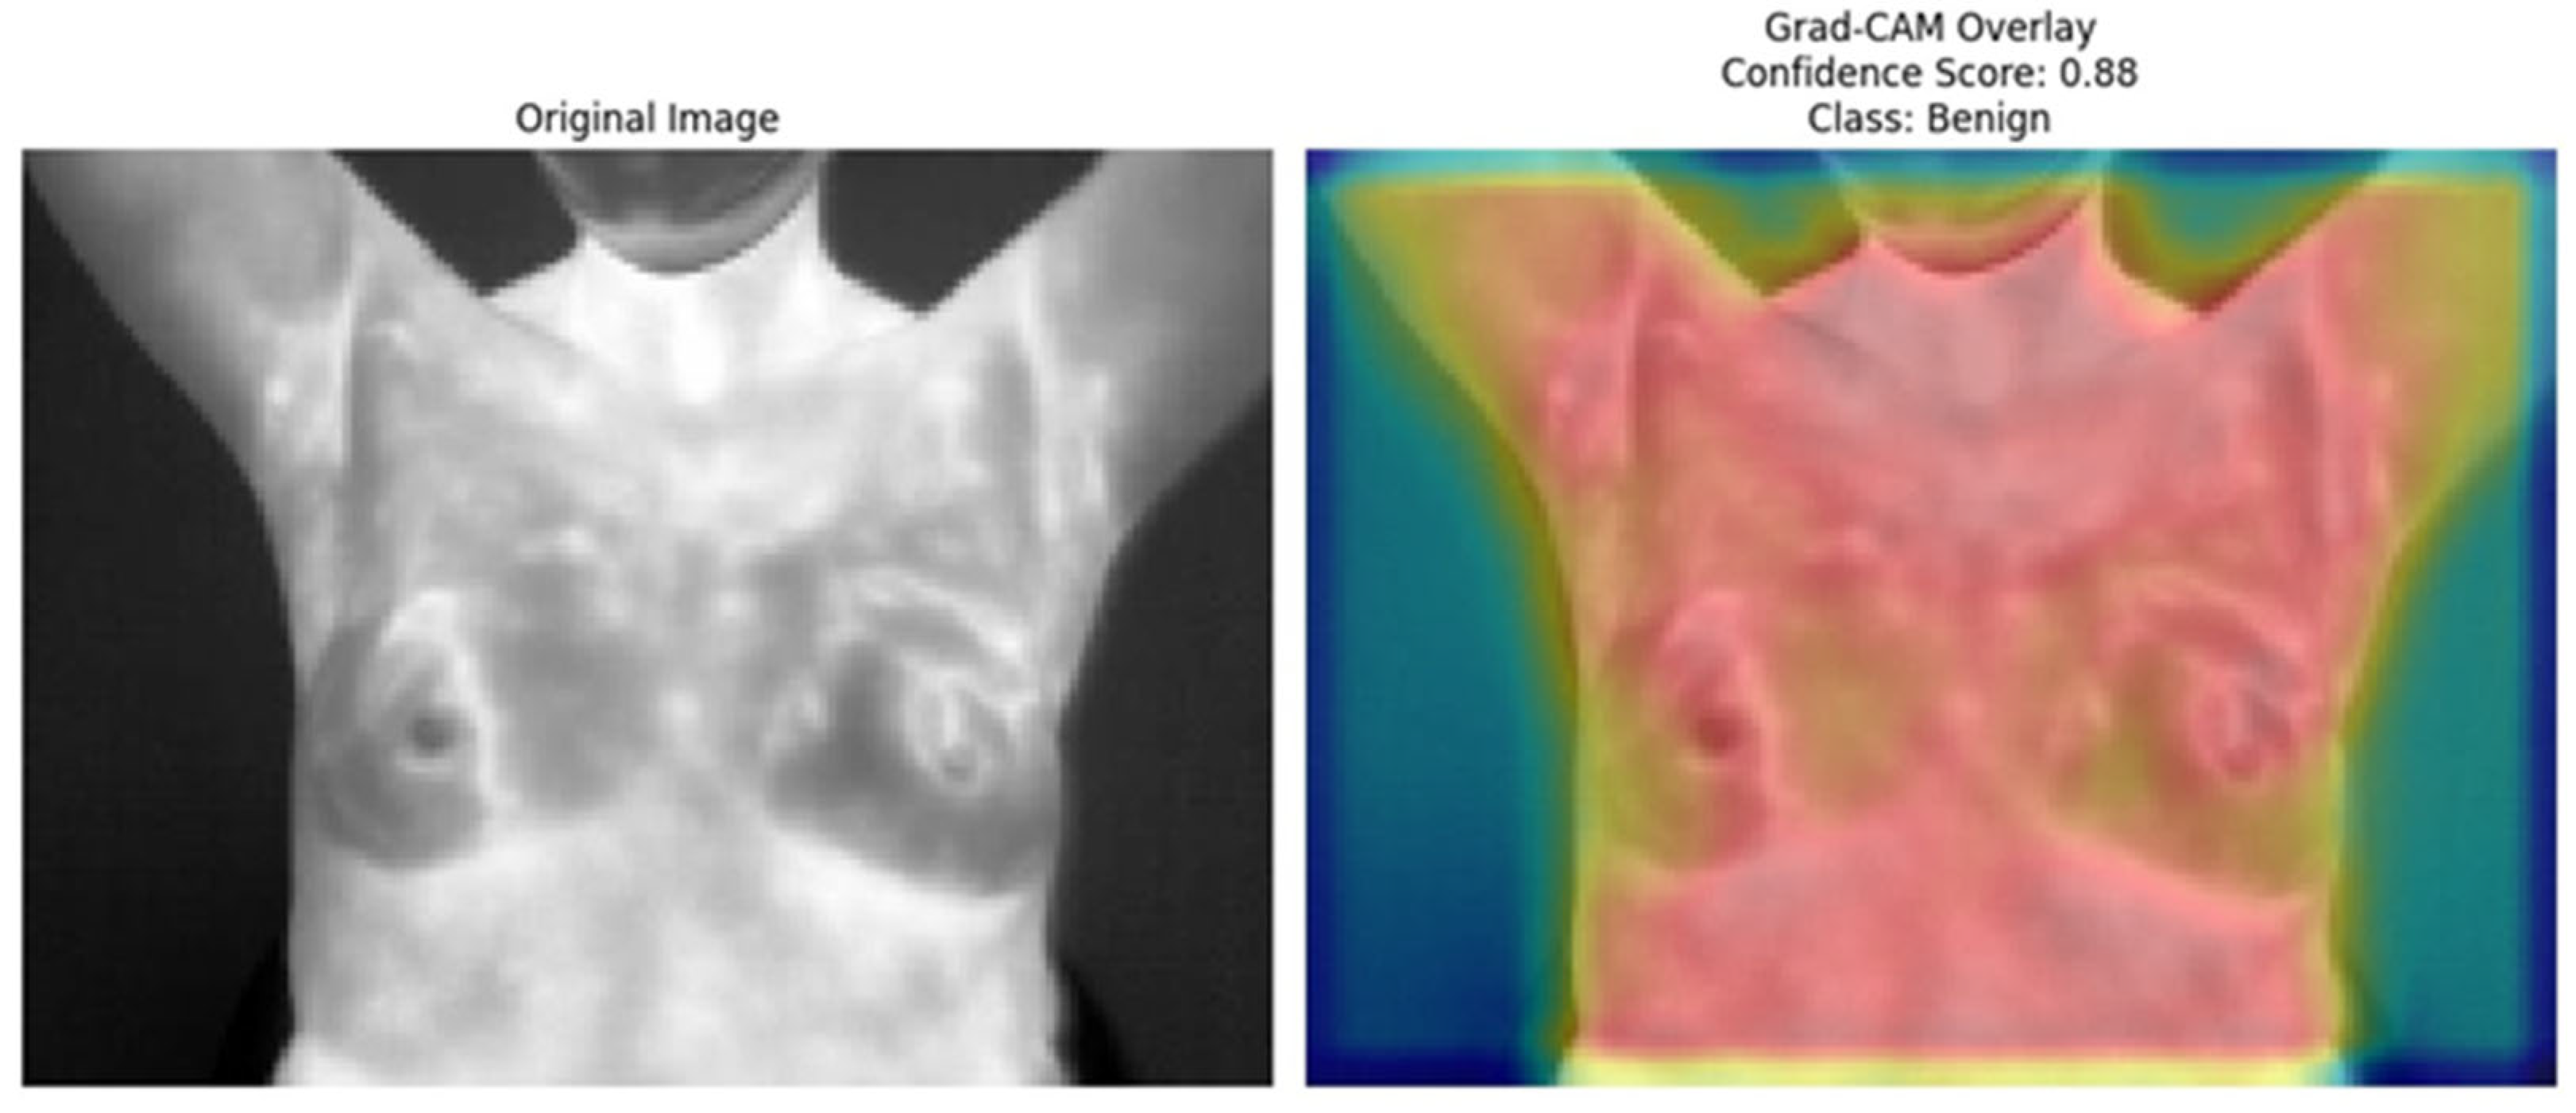

The Grad-CAM [41] overlays provide an essential layer of explainability to the ResNet152 + SVM model by highlighting regions of interest (ROI) that significantly influence the model’s predictions. These heatmaps, specific to each predicted class (e.g., normal, sick, malignant, benign), offer class-specific activation maps, shedding light on how the model differentiates among categories. By incorporating confidence scores (e.g., 0.80, 0.85) alongside these visualizations, clinicians can better understand and trust the model’s decision-making process. This approach directly addresses the “black-box” nature of deep learning models by visually explaining their predictions. Moreover, Grad-CAM overlays emphasize biologically relevant regions, such as abnormal heat patterns [56], as depicted in Figure 15, Figure 16, Figure 17, Figure 18 and Figure 19, enhancing the model’s interpretability and robustness in feature extraction. These insights validate the model’s focus areas against clinical knowledge and bridge the gap between AI-driven predictions and practical clinical applications, paving the way for greater trust and usability in real-world diagnostic settings.

Figure 18.

Grad-CAM Overlay for Benign Class (the original thermal image (left) and its Grad-CAM overlay (right) depict the regions contributing to the model’s prediction of the “benign” class with a confidence score of 0.88).